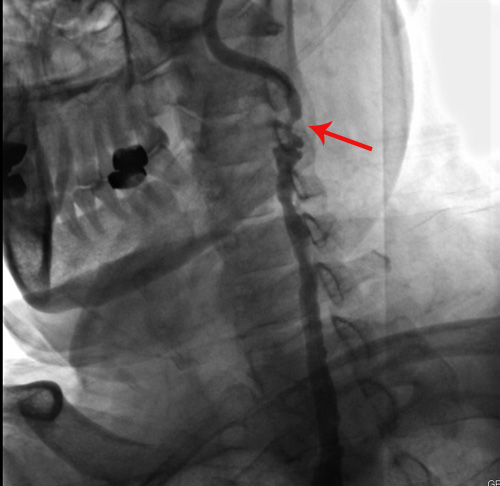

颈动脉彩超:双侧颈动脉粥样硬化斑块形成;双侧颈总动脉及窦部狭窄;双侧颈内动脉狭窄(极重度);双侧颈外动脉闭塞(右颈外动脉中远段血流考虑为侧枝循环供应)

左侧颈内动脉(箭头处可见狭窄)